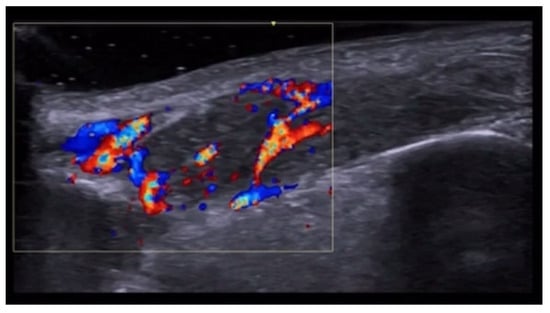

- Del Vecchio, D.; Kenkel, J.M. Practice Advisory on Gluteal Fat Grafting. Aesthetic Surg. J. 2022, 42, 1019–1029. [Google Scholar] [CrossRef]

- Vidal-Laureano, N.; Huerta, C.T.; Perez, E.A.; Earle, S.A. Augmented Safety Profile of Ultrasound-Guided Gluteal Fat Transfer: Retrospective Study with 1815 Patients. Aesthetic Surg. J. 2024, 44, NP263–NP270. [Google Scholar] [CrossRef] [PubMed]

- Elsaftawy, A.; Ostrowski, P.; Bonczar, M.; Stolarski, M.; Gabryszuk, K.; Bonczar, T. Buttock Augmentation with Ultrasonic Liposuction and Ultrasound-Guided Fat Grafting: A Retrospective Analysis Based on 185 Patients. J. Clin. Med. 2024, 13, 1526. [Google Scholar] [CrossRef]

- Elsaftawy, A.; Ostrowski, P.; Bonczar, M.; Stolarski, M.; Gabryszuk, K.; Bonczar, T. Enhancing Buttock Contours: A Safer Approach to Gluteal Augmentation with Ultrasonic Liposuction, Submuscular Implants, and Ultrasound-Guided Fat Grafting. J. Clin. Med. 2024, 13, 2856. [Google Scholar] [CrossRef]

- Wang, B.; He, P.; Zhao, R. B-ultrasound-assisted gluteal fat grafting in Asians: A prospective study of quantitative results from three-dimensional imaging and B-ultrasound analysis. J. Plast. Reconstr. Aesthetic Surg. 2024, 94, 12–19. [Google Scholar] [CrossRef] [PubMed]